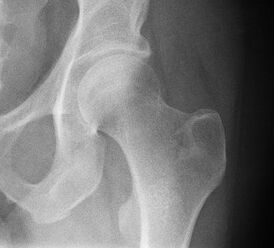

Рентгенограмма тазобедренного сустава.